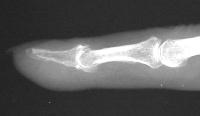

Clinical Example: Breast cancer metastatic to fingertip

Breast cancer is known to metastasize widely. This patient with poorly differentiated breast cancer developed a fingertip mass. Biopsy confirmed metastasis, but she declined further surgery.

Probable erosive changes of adjacent distal phalanx.